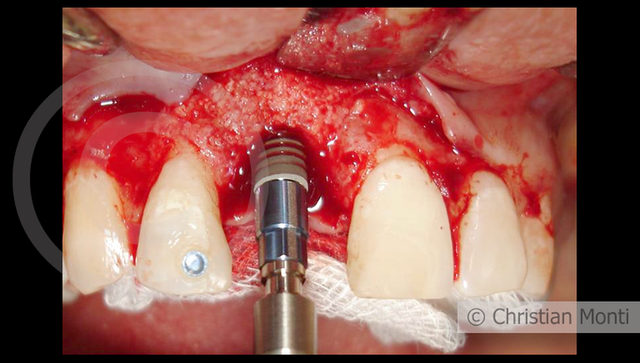

EDENTULIA SINGOLA

Impianto in sostituzione di un incisivo superiore